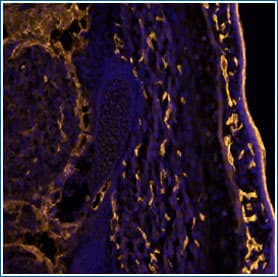

Example of IHC Detection by Immunofluorescence (IF): CD31/PECAM-1 in Mouse Embryo

CD31/PECAM-1 in Mouse Embryo. CD31 staining using Goat Anti-Mouse CD31/PECAM 1 Antigen Affinity-purified Polyclonal Antibody (Catalog # AF3628).